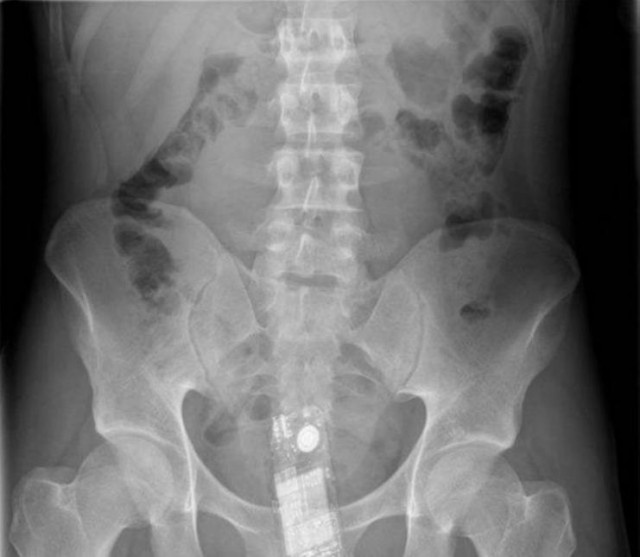

・究極のマナーモード!?